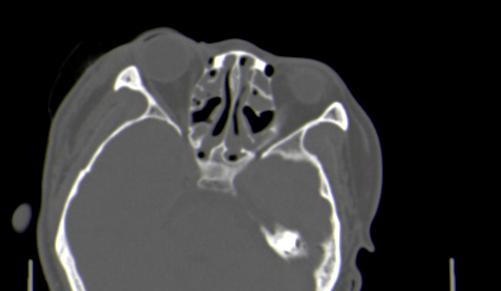

以下是引用皎皎白驹在2006-11-29 8:48:00的发言:[br]影像表现:双侧筛窦和上颌窦、鼻腔内均密度增高,右侧视神经增粗、弯曲,左筛窦顶部筛板及右侧纸板近视神经孔区可见骨折线。[br]结合临床表现考虑:右侧筛窦纸板近视神经孔区骨折致右侧视神经损伤。最好做个眼眶冠状扫描,更明确右侧视神经管是否狭窄。

以下是引用w_jianhua在2006-11-29 10:07:00的发言:[br]影像表现:双侧筛窦和上颌窦、鼻腔内均密度增高,右侧视神经增粗、弯曲,左筛窦顶部筛板及右侧纸板近视神经孔区可见骨折线。[br]结合临床表现考虑:右侧筛窦纸板近视神经孔区骨折致右侧视神经损伤。最好做个眼眶冠状扫描,更明确右侧视神经管是否狭窄。 [br] [br]支持[br]

以下是引用守望可可西里在2006-11-29 9:46:00的发言:[br][quote]以下是引用皎皎白驹在2006-11-29 8:48:00的发言:[br]影像表现:双侧筛窦和上颌窦、鼻腔内均密度增高,右侧视神经增粗、弯曲,左筛窦顶部筛板及右侧纸板近视神经孔区可见骨折线。[br]结合临床表现考虑:右侧筛窦纸板近视神经孔区骨折致右侧视神经损伤。最好做个眼眶冠状扫描,更明确右侧视神经管是否狭窄。